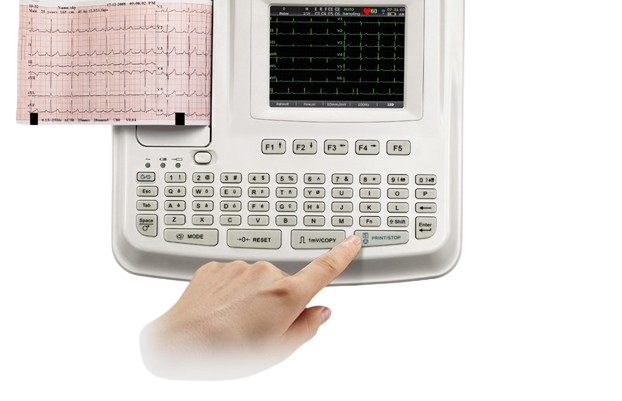

Bionet CardioTouch 3000 12 Channel ECG Machine

Bionet CardioTouch 3000 12 Channel ECG Machine